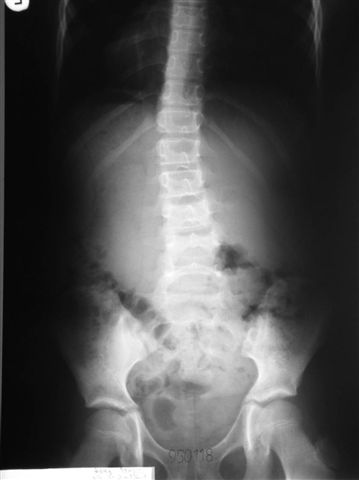

W początkowych skoliozach tzw. idiopatycznych przez specjalny system usprawniania i ćwiczeń, zalecenia rehabilitacyjne można zatrzymać rozwój skoliozy a nawet uzyskać poprawę osi kręgosłupa.

Na radiogramach przebieg leczenia jednej z moich pacjentek.